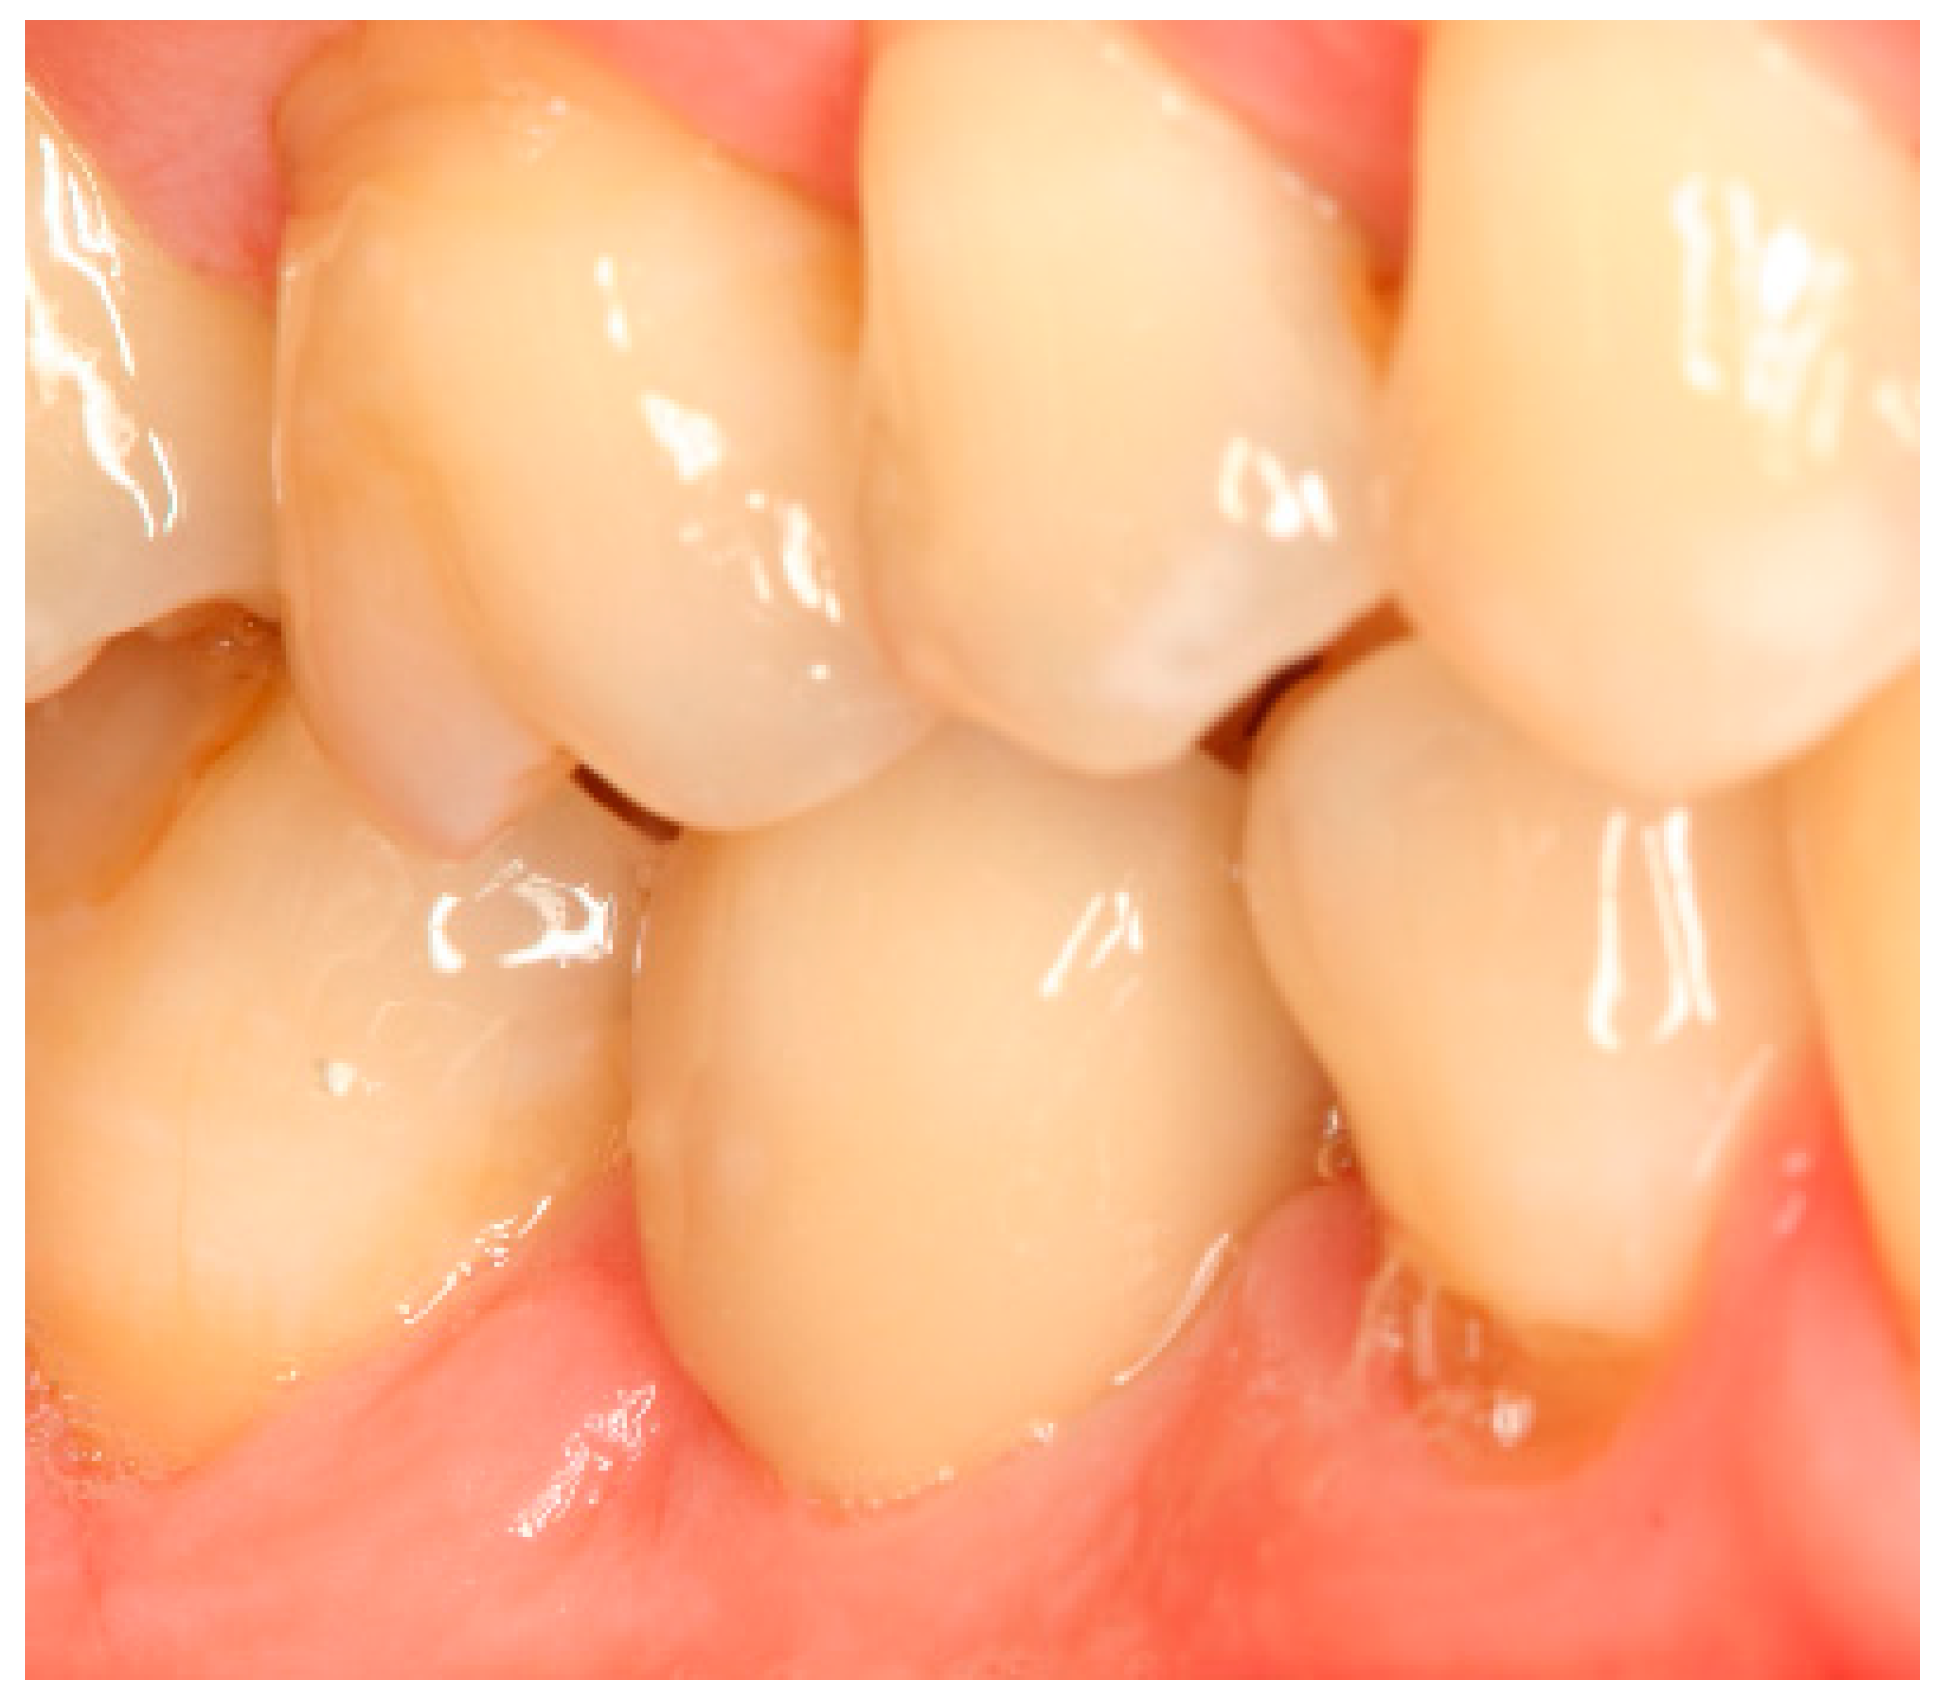

Appendix A. Exemplary Photographs and Radiographs from a Patient at Different Examination Time Points and a Positive Outcome

Appendix B. Exemplary Photographs and Radiographs from a Patient at Different Examination Time Points and a More Negative Outcome